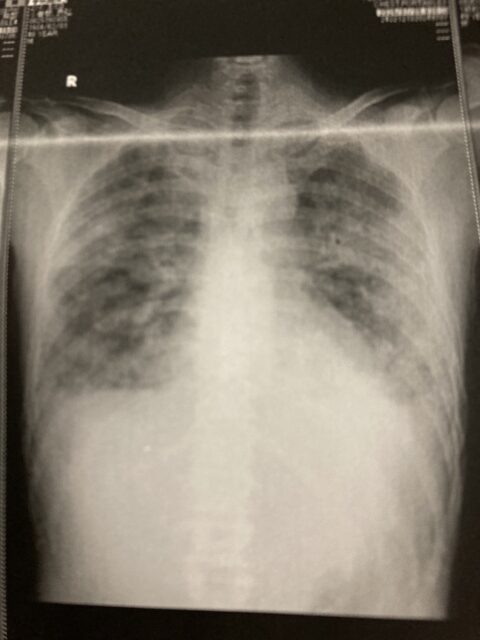

肺炎の症状は

私の場合、主観的にしかお伝えできませんがこの2日間は安静時は富士山登頂場所よりも高所での生活➕少しの動作で息苦しくなってしまう状態でした。

幸いなことに咳・痰・喉の痛みなどは全く無かったのでありがたかったです!

たまにの頭痛・怠さ・熱が37〜38ぐらいで

酸素の量が9㍑→7㍑に減り

いまだに原因不明の肺炎です